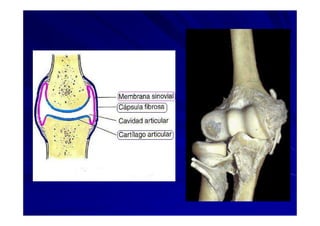

El documento presenta una introducción a la anatomía normal. Explica que la anatomía es el estudio de la estructura del cuerpo humano y clasifica los tipos de anatomía. Además, enumera los contenidos que serán cubiertos en el curso, incluyendo conceptos, posición anatómica, vocabulario, osteología, artrología y miología.